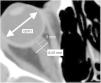

ResultsThe mean ONSD was measured as 6.39±0.92mm for the right eye, 6.50±0.91mm for the left eye on preoperative CT. The mean ONSD by CT (after surgery) was 4.89±0.87mm for the right eye, 5.02±0.1mm for the left eye (p<0.05). Postoperative group A and group B were compared according to ONSD measurement; mean ONSD in group A was 4.52±0.69mm for the right and 4.59±0.9mm for the left, mean ONSD in group B was 5.82±0.51mm for the right and 6.1±0.32mm for the left (p<0.05). The best ONSD value for detecting failed ETV was 5.40mm (sensitivity 90%, specifity 75%, AUROC 0.938) for right and 5.91mm (sensitivity 90%, specifity 75%, AUROC 0.950) for left. EE was measured as 0.39±0.12mm on preoperative MRI and 0.39±0.12mm on postoperative MRI (p=0.3). V3 was measured as 14.7±2.47mm on preoperative MRI and 10.47±1.99mm on postoperative MRI (p<0.05).